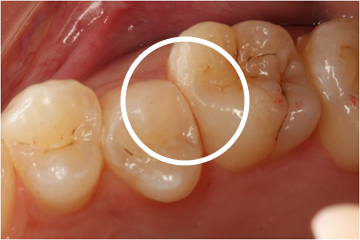

むし歯に感染した部位のみを除去し、コンポジットレジンにて修復。健全な歯質まで削らずに済みます。

むし歯検知液 ~カリエスチェック~

歯科医院でむし歯の治療をされている際、どうやってむし歯を見分けるのだろうと思った事はありませんか?

むし歯部分は、歯質が軟らかくなっているためその部分を削るのが最も一般的な方法です。

歯質が軟らかくなっている部分はむし歯菌に感染している正真正銘のむし歯です。

しかし、その周辺に薄く存在するむし歯菌に侵されていない少し軟らかくなっている部分は、あえて削らなくても再石灰化によって硬くなる可能性の高い部分です。

そのためむし歯菌がいる歯質の判別の指標となるのが、「むし歯検知液 カリエスチェック」です。

これを使用することで、本当に悪い部分だけを削り、削る部分を最小限に抑えることができます。